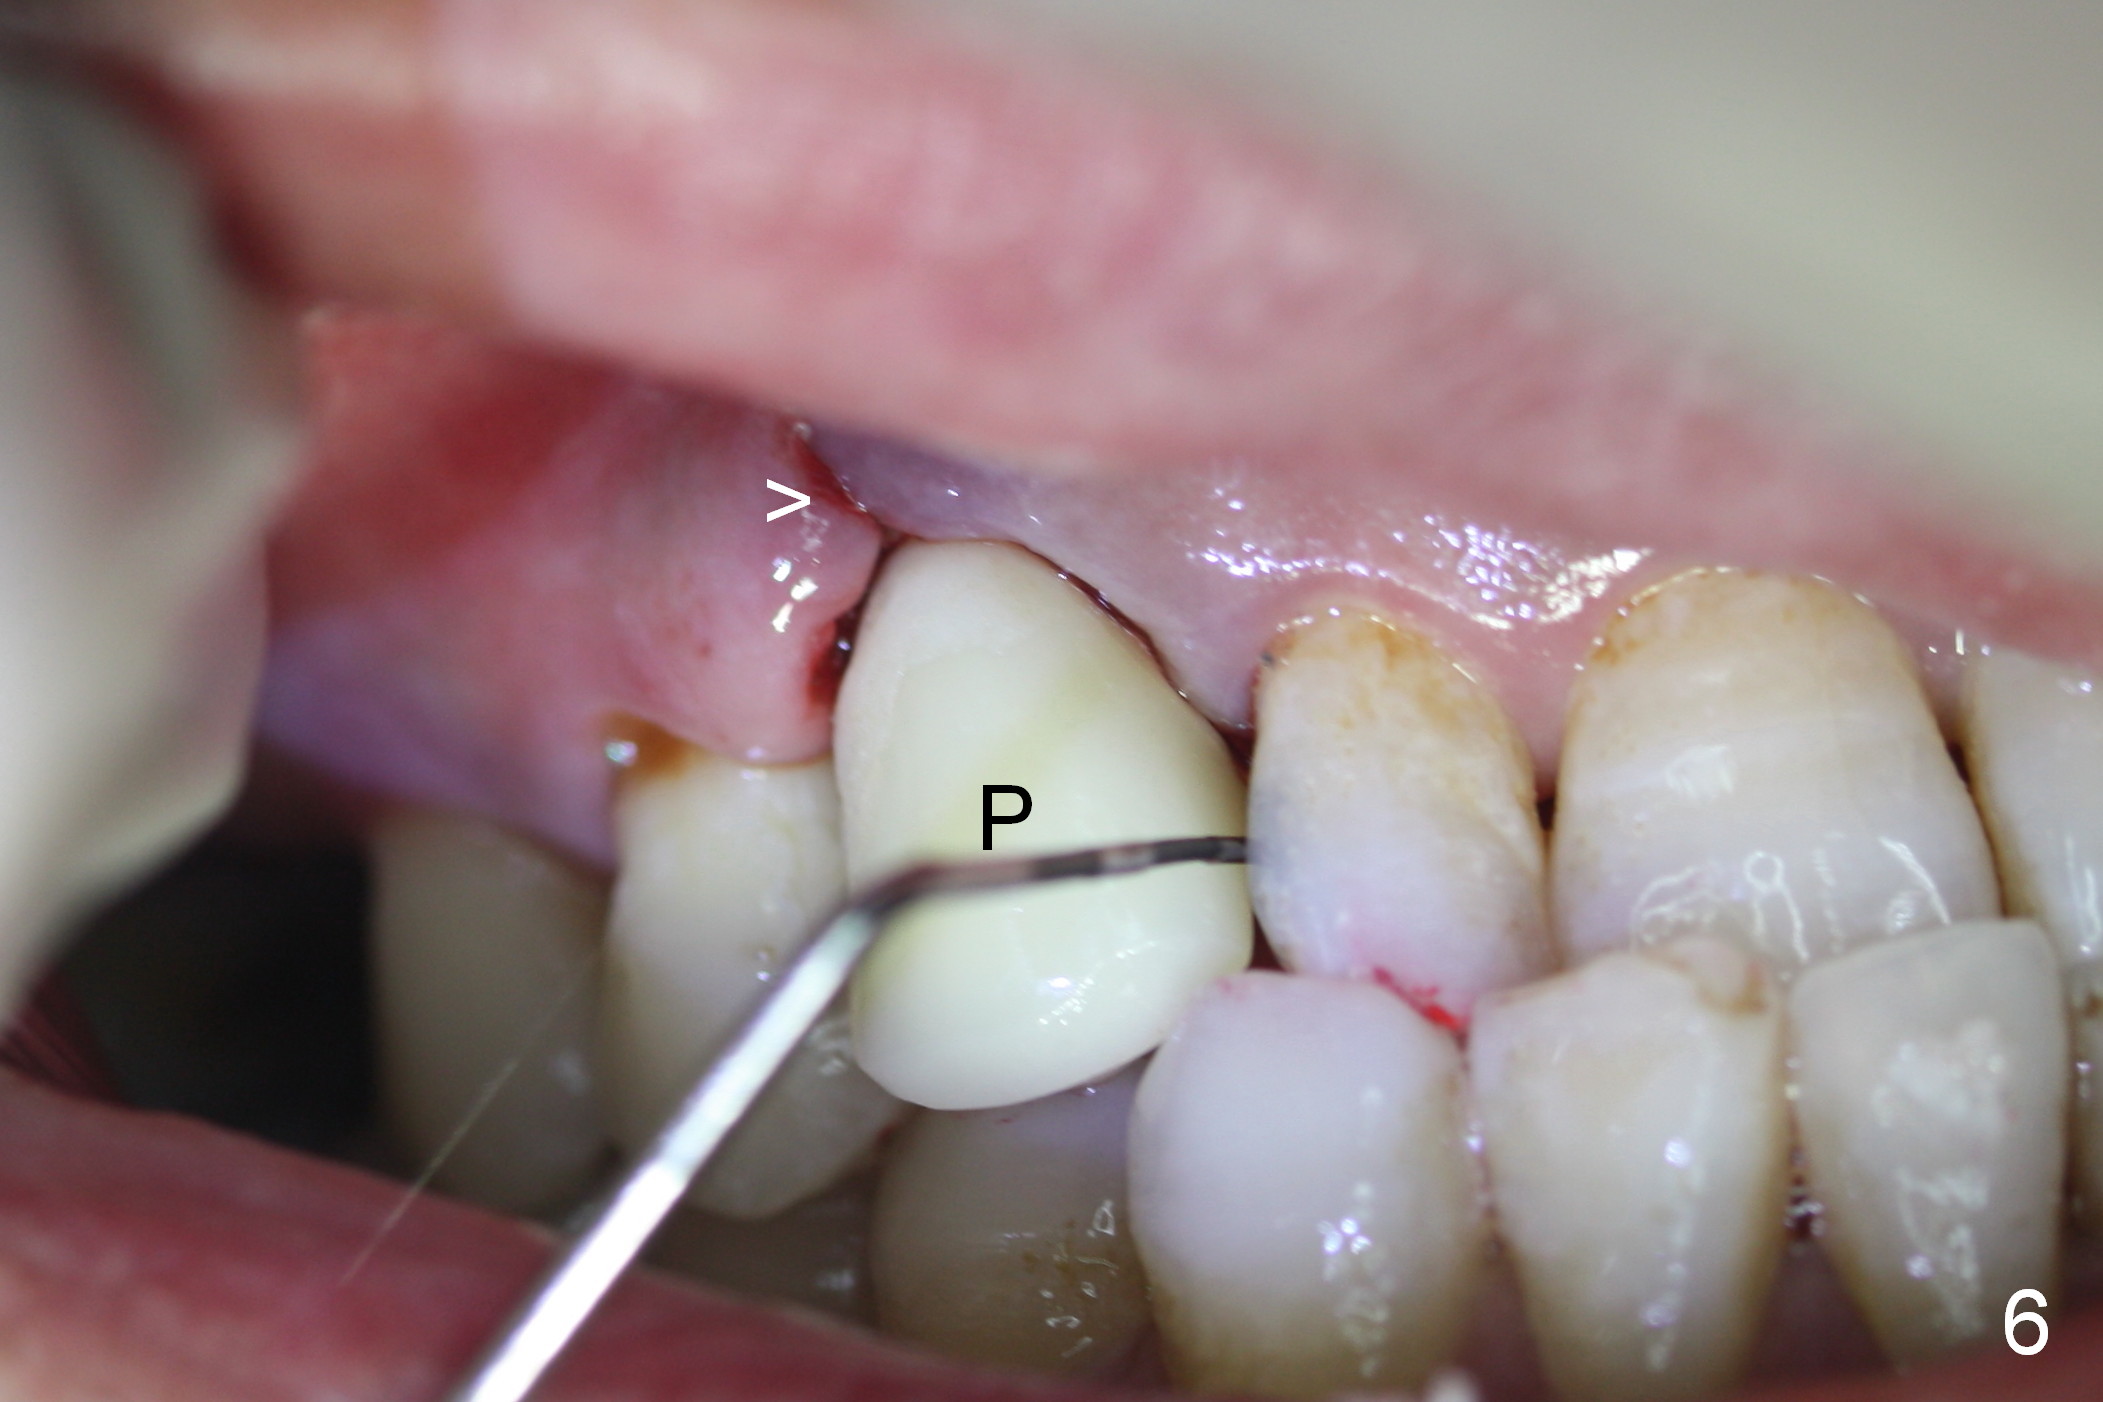

After 5x20 mm implant is placed, the distal gap is filled with bone graft (Fig.5 *). An abutment is placed (A) for fabrication of an immediate provisional (Fig.6 P). The latter hold the labial gingiva bulging (Fig.6 >). When the provisional is removed for bone grafting, the labial gingiva collapses (Fig.7 arrowheads). In fact a piece of cone-shaped Osteotape (Impladent) is placed palatal to the labial gingiva/thin labial plate and a small amount of graft is placed in the deepest area of the socket (labial to the osteotomy) prior to placement of the implant. More graft is placed in the peri-implant gap, particularly labially to keep the labial gingiva convex (Fig.8 arrowheads). The lacerated gingiva is to be approximated with perio glue (Fig.9 <). Collagen dressing is placed over the exposed graft before cementation of the provisional. Perio dressing is applied for further protection and seal.